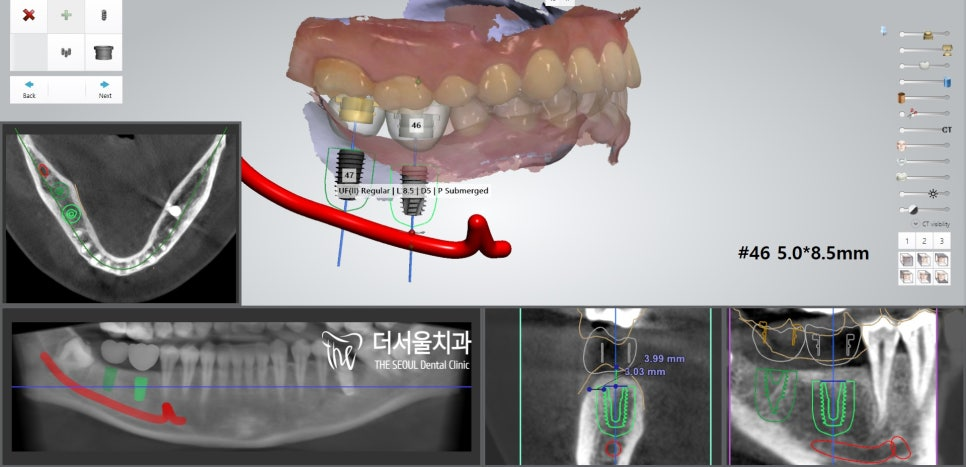

좌측과 마찬가지로 컴퓨터 분석을 통해

식립 위치 및 방향, 각도 등을 결정했습니다.

오랜기간 잔존치근만 남아있었기 때문에

치조골이 소실되어 있진 않을까 걱정이 되었는데요.

다행히 별 다른 문제 없이

식립을 도와드릴 수 있을 것 같네요.